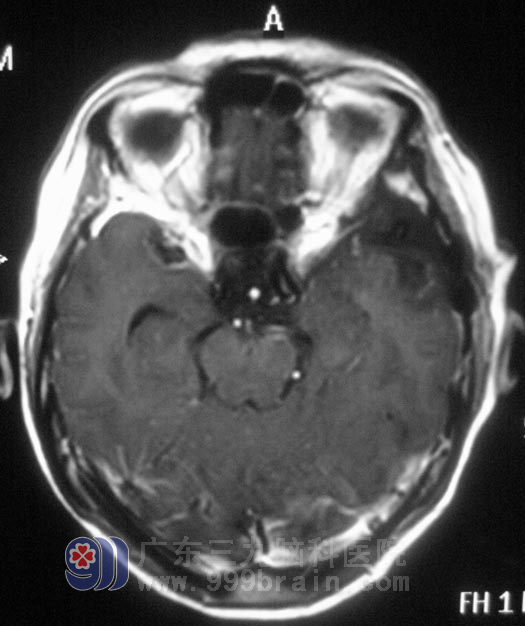

颈椎MR提示“颈4/5、5/6、6/7椎间盘突出”,头颅MR示“左侧蝶骨嵴脑膜瘤,大小约2.8cm×2.9cm×3.1cm”。家人回想起两年前,黄女士就开始出现左眼视力下降,偶有头晕,并没有引起重视,知道这个结果后肠子都悔青了。

11月23日,由广东三九脑科医院综合神经外科 鲁明主任主刀,在全麻下行左侧蝶骨嵴脑膜瘤切除术+颅内压探头植入术,术中取左侧额颞弧形切口,在显微镜下见肿瘤呈灰白色,与大脑中动脉粘连紧密,予肿瘤全切,对视神经、动眼神经保护完好。术后黄女士经过一段时间的恢复,诉左眼视力较术前明显好转,肩周炎也在广东三九脑科医院得到了有效的治疗。术后病理结果:过渡型脑膜瘤 WHO I 级。http://www.999brain.com/